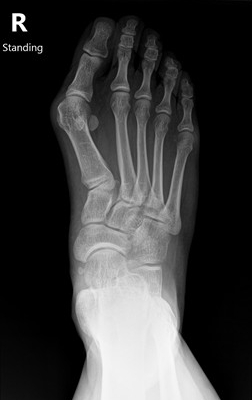

【2025最新】拇趾外翻早期症狀圖解:怎麼判斷需不需要手術?

什麼是拇趾外翻?

拇趾外翻(Hallux Valgus)是指大拇趾向第二趾偏斜,同時第一蹠骨頭向內側突出,造成腳內側明顯的骨頭突起,俗稱「腳拇指變形」。…